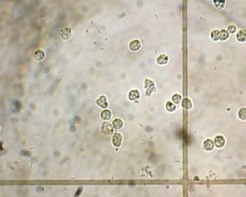

В норме, у здорового человека в моче может содержаться небольшое количество лейкоцитов: у мужчин от 0 до 3, у женщин от 0 до 6 в поле зрения. Данные нормы характерны для общего анализа мочи. В некоторых случаях для более точного подсчета количества лейкоцитов в моче, могут использоваться другие лабораторные методики (проба по Нечипоренко – в норме количество не превышает 4 тыс; проба Каковского-Адисса – норма не превышает 2 млн. в суточной моче).

Повышение количества лейкоцитов в моче (лейкоцитурия) – признак воспалительного процесса в мочеполовой системе, который может иметь как инфекционный (пиелонефрит, цистит, уретрит, простатит, везикулит, туберкулез почки…), так и неинфекционный характер (гломерулонефрит, интерстициальный нефрит…). Если на фоне повышенного количества Л. отсутствует бактериурия (бактерии в моче) – говорят о стерильной лейкоцитурии. Такая картина может быть связана либо с неинфекционными заболеваниями мочеполового тракта, либо имеет место бактериальный процесс, при котором возбудитель не выявляются при клиническом анализе мочи или стандартном бактериологическом исследовании (туберкулез мочеполовой системы, хламидиоз, микоплазмоз, уреаплазмоз).

В некоторых случаях проводится уроцитограмма, которая показывает, какие именно лейкоциты присутствуют в моче, что зачастую позволяет определить характер процесса вызвавшего лейкоцитурию: